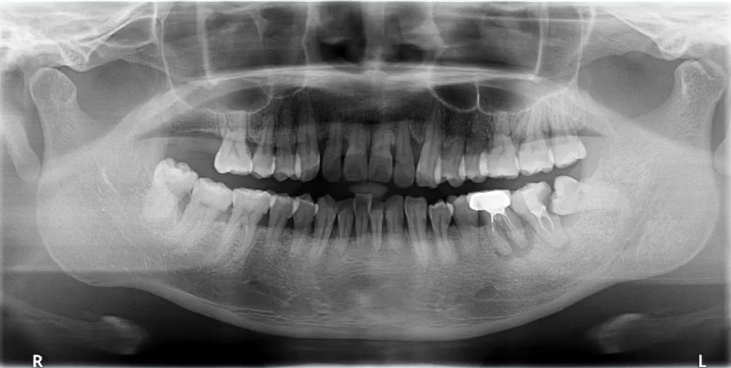

口腔曲面断层X线摄影(Rotational Panoramic Radiography)通过专门设计的口腔曲面全景摄影X线机,将上颌骨、下颌骨、颞颌关节、上颌窦、鼻腔及全口牙齿的影像同时显示在1张体层照片上的摄影技术。

口腔曲面断层摄影在医疗诊断中德应用越来越广泛,它能为牙科病,牙齿矫形以及牙槽骨,题颌关节的骨折骨病等多种疾病提供重要的信息。

一、理想曲断影像

中线左右对称,牙齿排列呈微笑弧形,片子左右两边相对对称,能清晰显示颞下颌关节、上下牙列的牙根,图像的对比度和分辨率较好。

1. 全面显示牙列:牙体疾病初步诊断

比如下面这张片子显示出的龋坏合并根尖周炎。

因为曲面断层片反映的是上下颌牙齿、上颌窦、关节,在一张片子中所展示的解剖结构较多。比如刚才的片子,最容易诊断的是右下6远中邻面深龋合并根尖周炎,左下有埋伏的多生智齿,右侧是垂直智齿。

注意不要遗漏,比如片子中显示上颌两个3是缺失的,是先天性缺失还是做过手术?有可能会漏掉一些临床信息。